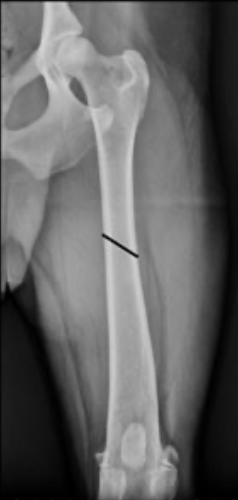

What type of fracture is this?

Q

A

short oblique